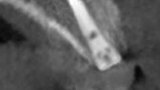

Fig. 19: CBCT cross-section following implant placement demonstrating adequate width to house the implant and sufficient facial plate thickness.